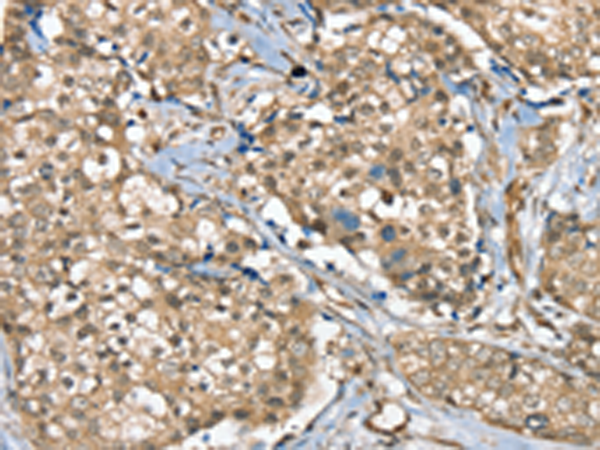

分类: 科研抗体货号: P12164别名: SPL; S1PL应用: WB,IHC反应种属: Human, Mouse, Rat